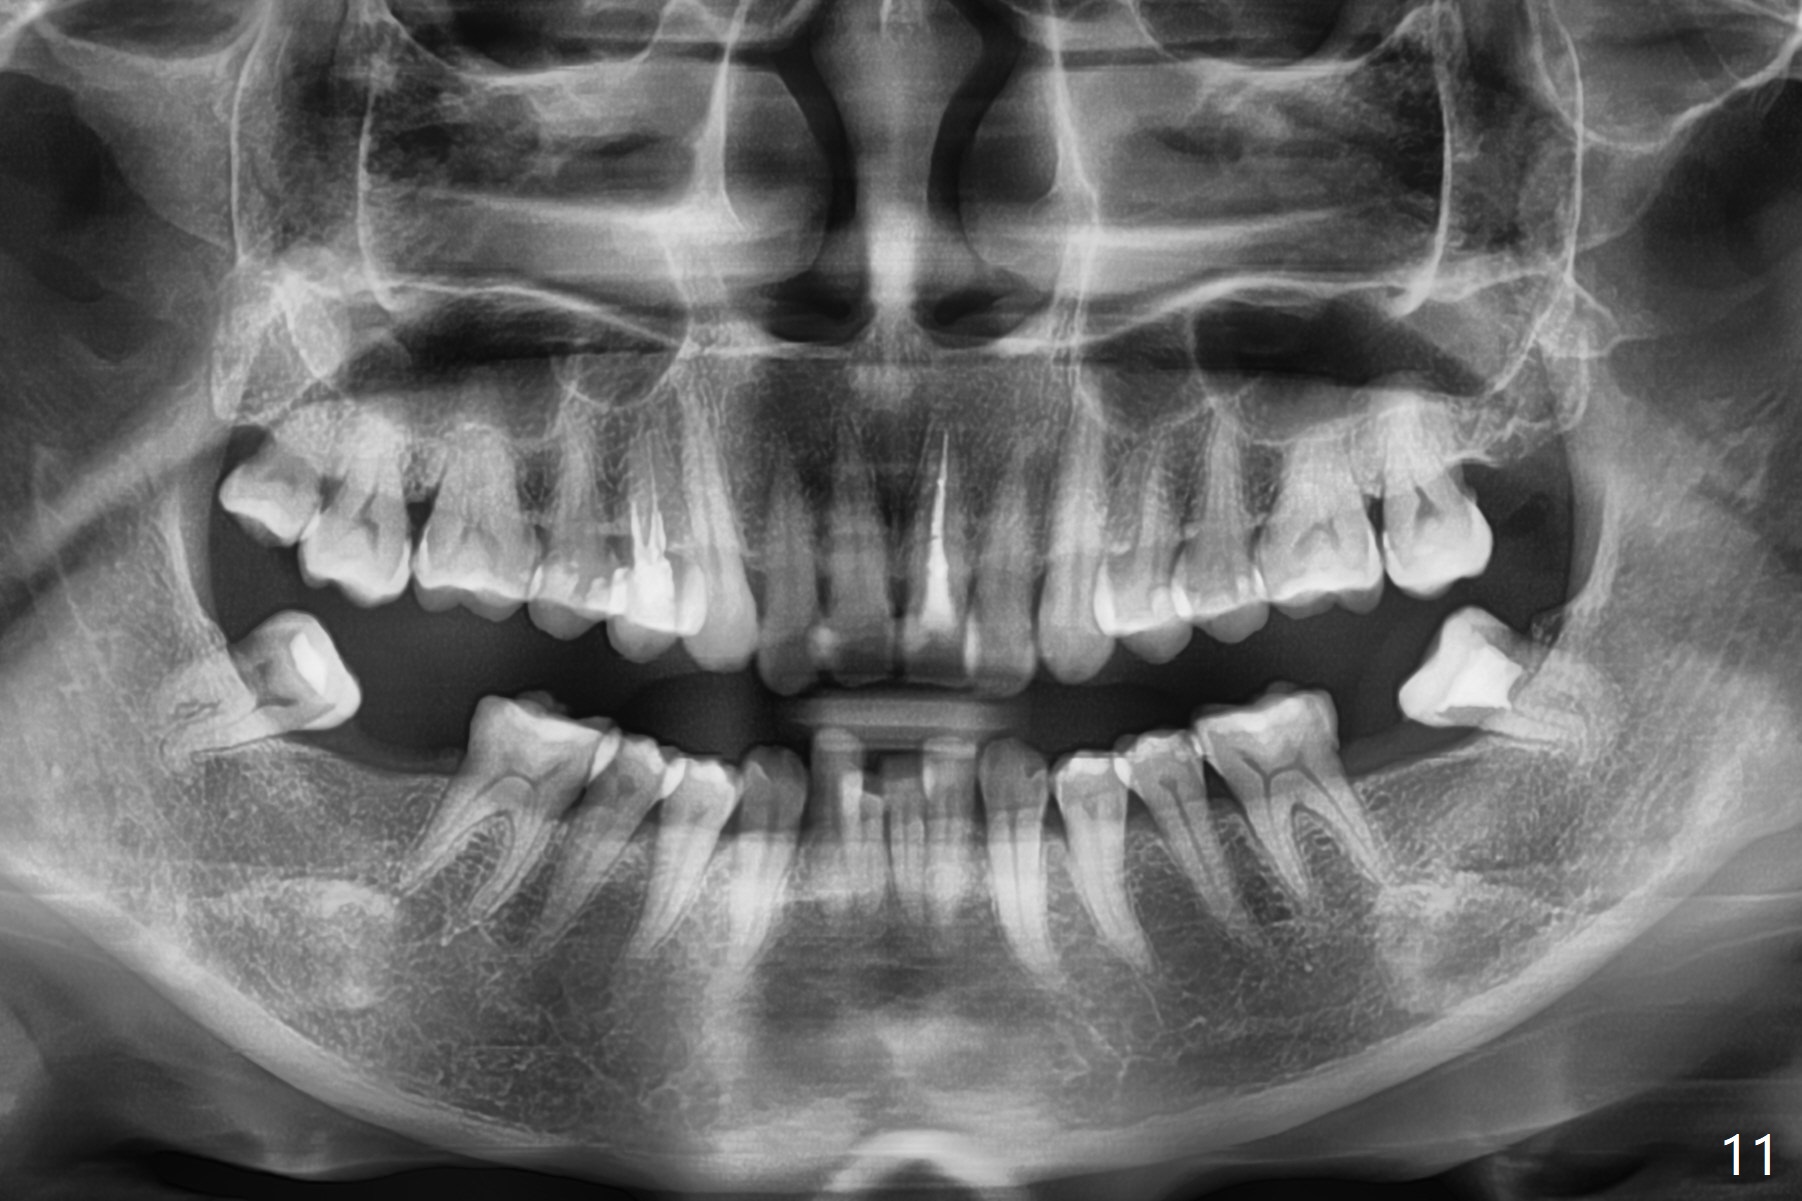

A 41-year-old woman requests ortho, bleach and replacement of 2 lower molars (L7s). The lips are protrusive (Fig.1,3), which is seemingly due to the underlying protrusive anterior teeth (Fig.4,5). Cephalometric tracing shows that SNA and SNB are both 87º (Fig.12), suggesting extraction. When the protrusive teeth are distalized, pay attention to move the upper dental midline to the right (Fig.2). BWs show subgingival calculus. SRP is required. Internal bleaching will be conducted for UL1 (Fig.7,11). Distalization is accomplished with extraction of 2 upper 1st bicuspids and using L8s as anchors so that no implants will be necessary for L7s. But the patient would rather have 2 of the lower 2nd molars for mastication. It appears that extraction of 4 bicuspids is pending (Fig.6-11). Supraeruption of U7s (Fig.6,8 arrows) will be corrected with banding.